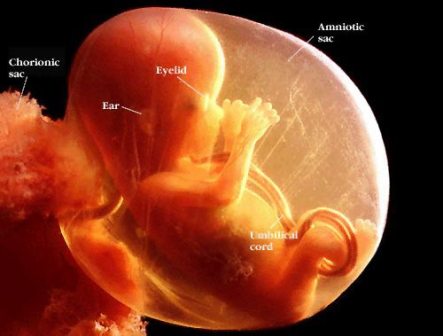

Anne adayı henüz bir değişiklik hissetmese de gebelik kesesi (gestasyonel sac) oluşmaya, göbek kordonu (yolc sac) sayesinde embrio'ya oksijen ve besin taşımaya başlamıştır. Gelişen bebek adayı artık sizden yeterli vitamin, folik asit, protein, kalsiyum, demir vb. beklemektedir. Özellikle gebe kalmadan birkaç ay öncesinden itibaren günde 400 mikrogam Folik asit almaya başlamalısınız.

Bebek anne rahmi içinde amnion denilen bir sıvı içinde gelişir. Bu sıvı bebeğin rahat hareket etmesini sağlar, darbelerden korur ve bebeğin akciğerlerinin, sindirim sisteminin ve diğer pek çok organının sağlıklı gelişiminde rol oynar.

Gebelik kesesi (gestasyonel sac) artık transvaginal ultrasonla 5.haftada mutlaka rahim içinde görülmelidir.Yaklaşık 1 cm büyüklüğe ulaşır. Bu esnada kanda gebelik testi B-HCG 1500-2400 civarındadır. Gebelik kesesi kalınlaşmış rahim iç duvarı içinde yaklaşık 8-10 mm boyutunda koyu renkli bir halka şeklinde görülür ve günde 1-2 mm büyür. Gebelik kesesi yaklaşık 1 cm büyüklüğe ulaştığında yolc sac da görünmeye başlar. Ortalama 1.5 cm çaplı gebelik kese içinde embrio ve yolc sac birlikte görülür.

Bu esnada embrio gebelik kesesi içerisinde hızla gelişmektedir. Yaklaşık 2-5 mm boyutundadır ve 3-4 mm büyüklüğünde yuvarlak beyaz halka şeklinde izlenen yolc kesesine yakın yerleşimlidir.